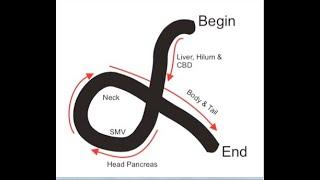

Basics of Linear EUS , Railroad technique, Alpha manoeuvre, Contrast EUS, EUS FNA tips and tricks